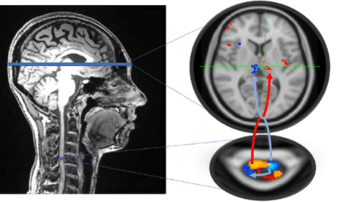

The Systems Neuroscience & Pain Laboratory at Stanford University (SNAPL) is actively recruiting a postdoctoral fellow who will join our research project on chronic pain. Funded by the National Institute of Health and directed by neuroscience professors Sean Mackey and Gary Glover, our goal is to investigate mechanisms of chronic pain using methods we developed to image the entire CNS via simultaneous spinal cord/brain fMRI.

Our plan is to characterize neurobiological mechanisms underlying chronic pain and use this information to develop objective biomarkers of pain, ultimately, to derive new personalized interventions. Given abundant findings that fMRI of the brain can act as biomarker for chronic pain conditions, we propose utilization of our simultaneous spinal cord/brain fMRI to develop biomarkers of pain severity. Our research can be categorized as follows: